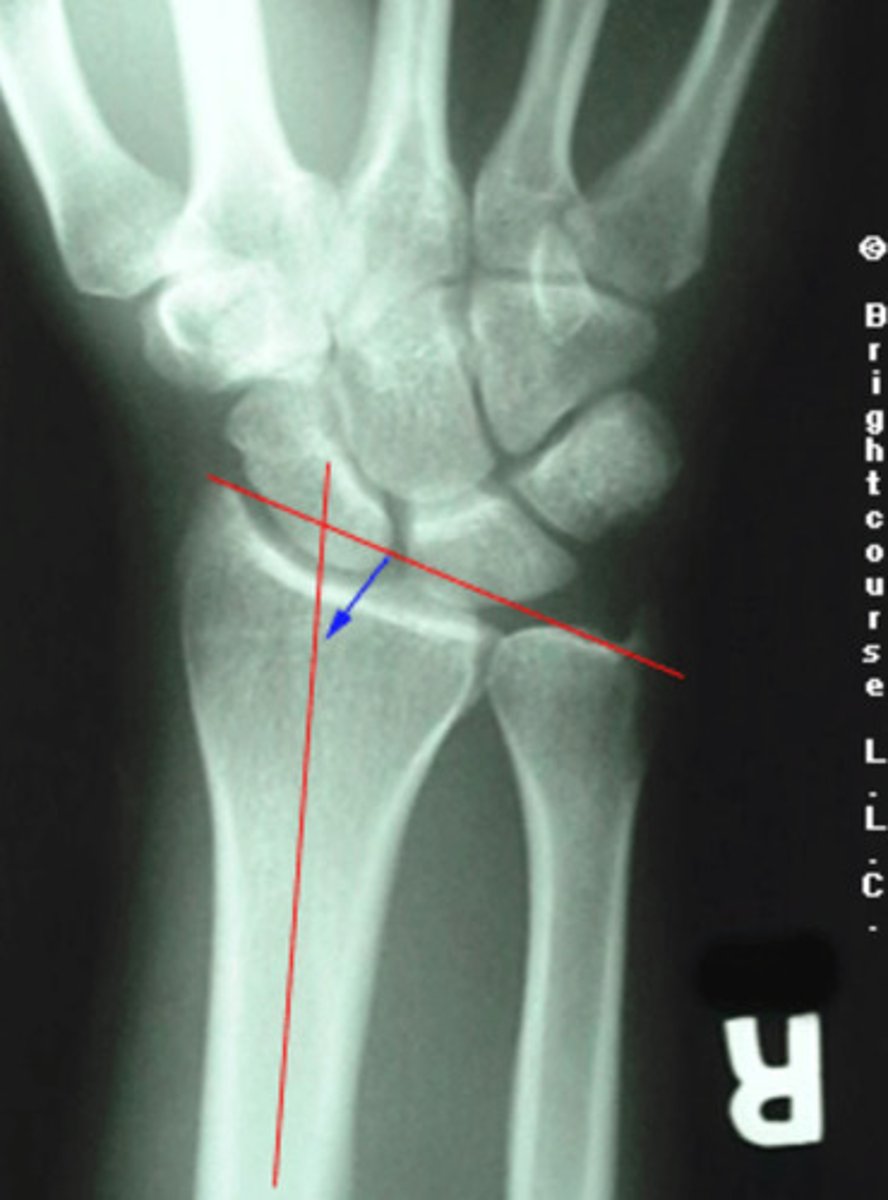

Radius angle

What angle is being assessed in this image?